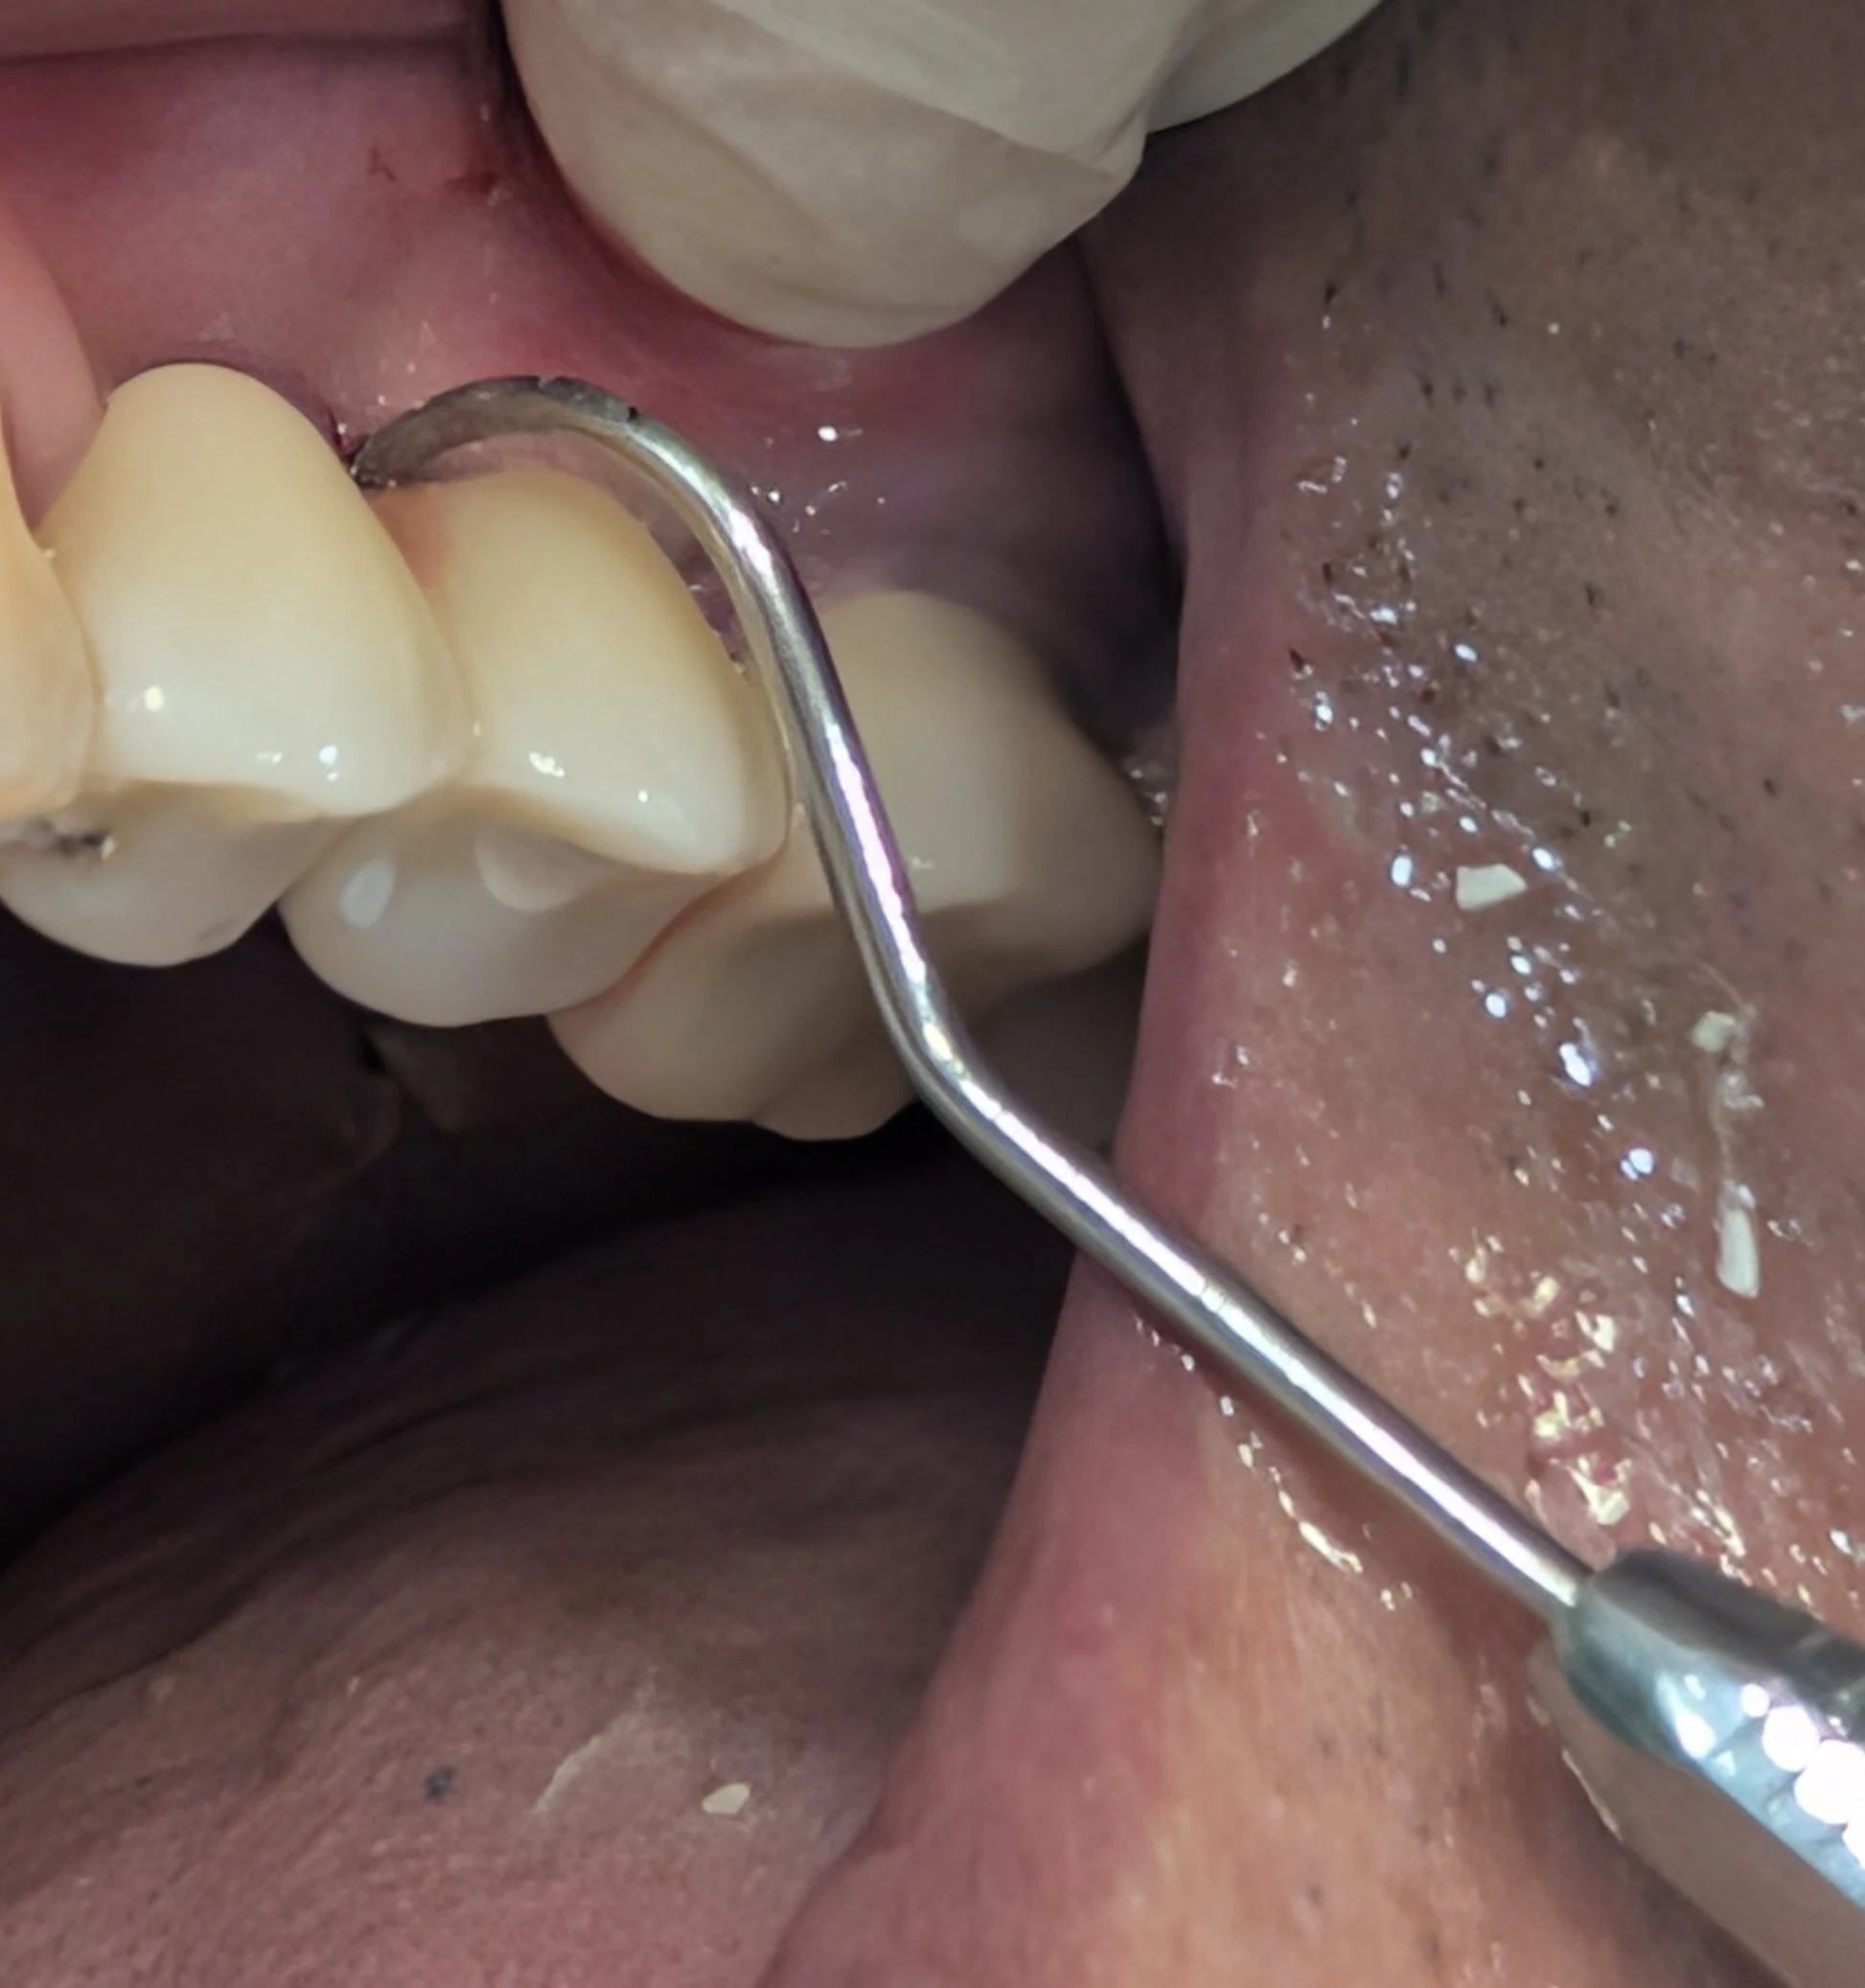

تست عبور سوند در ایمپلنت های اسپلینت شده

عبور سوند از امبراژور اسپلینت قبل از تحویل

وقتی روکش‌های ایمپلنت به هم اسپلینت هستند، باید با سوند از امبراژور بین آن‌ها عبور کنیم تا مطمئن شویم که یک مسیر واقعی و قابل‌استفاده برای بیمار وجود دارد.

اگر سوند عبور نکند ← یعنی مسیر بهداشتی وجود ندارد ← یعنی باید کانتور، امبراژور یا تماس‌ها اصلاح شوند.

عبور دادن سوند از امبراژور اسپلینت قبل از تحویل، یک تست ساده و حیاتی است که سرنوشت بیولوژیک ایمپلنت را تعیین می‌کند.